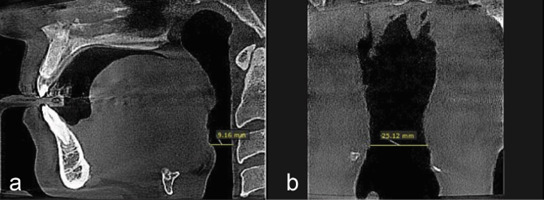

Materials and method: In this retrospective cross-sectional study, cone beam computed tomography (CBCT) records of 100 patients were analyzed. Patients were snoring non-OSA individuals, diagnosed through a thorough examination and negative polysomnography results. CBCT scans were executed in the standard position as per the specified protocol of the Sleep Center. Upper airway was divided into four parts (nasopharynx, velopharynx, oropharynx, and hypopharynx), and anteroposterior (AP) and transverse (T) dimensions within the minimal cross-sectional area of each respective region were evaluated. BMI, upper airway dimension, and hyoid bone were analyzed using Pearson and Spearman's correlation tests.

Results:  The retrognathion-hyoid-4th cervical vertebra (RHV) angle representative of the hyoid position was significantly greater in females (p Value=0.000). It also statistically decreased significantly in snorers aged 36-50 and 51-65, p= 0.006 and 0.012, respectively. Snorers had above-average BMI in all age groups and both genders. The AP-hypopharynx significantly correlated with BMI (p= 0.022).

Conclusion:  The hyoid position was gender-dependent, with a superior position in females. It was also age-dependent, with a more inferior position in snorers aged 36-65 compared to younger ages (20-35). The AP-velopharynx is a constriction region in the airway of snorers. Snorers were overweight in all age groups and both genders. BMI had a significant correlation with the AP-hypopharynx.